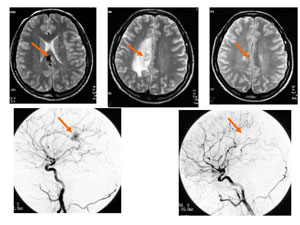

典型例をお示しします。くも膜下出血で発症した29歳、男性です。左上のMRIで矢印に示す部分に黒く見える部分が脳動静脈奇形です。左下は脳血管撮影で異常血管が黒くモヤモヤした血管の塊として確認できます。大きさは2.5cmでした。脳幹という脳深部で手術摘出が不可能な部位にありますので、ガンマナイフ治療を選択しました。ガンマナイフ治療後3年後のMRIを右上に血管撮影を右下に示します。病巣が完全に消失して治癒しています。

図4に典型的な放射線誘発浮腫例を示します。けいれん発症した20歳女性です(非出血例です)。ガンマナイフ治療時のMRIを上段左に、脳血管撮影を上段左に示します。矢印に病巣を示します。ガンマナイフ治療後1年後のMRIを上段中央に示します。病巣は消失していますが、周囲に雲がかかったような白い部分を認め、これが放射線誘発浮腫です。これに伴いけいれんが再度出現しましたが、副腎皮質ホルモンの3ヶ月間の投与で症状は消失しました。ガンマナイフ治療後3年のMRI(上段右)と血管撮影(下段右)を示します。病巣は完全に消失し治癒、放射線誘発浮腫も消失しています。